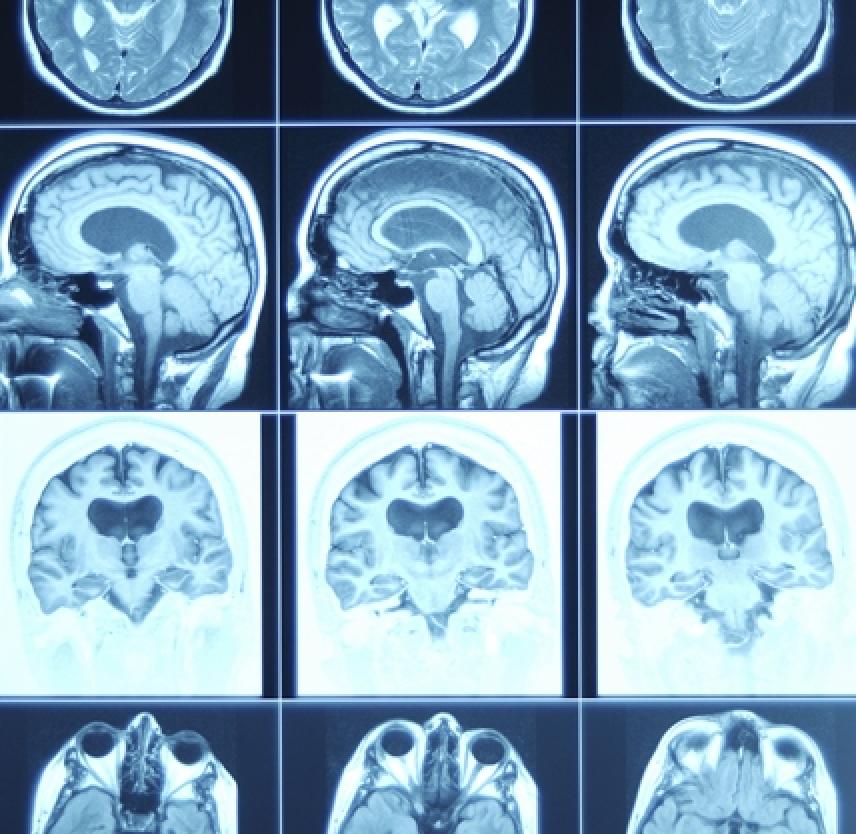

¿Qué es el traumatismo cerebral?

El traumatismo cerebral, también llamado lesión cerebral adquirida o simplemente lesión o trauma cerebral, ocurre cuando un trauma repentino causa daño al cerebro. El daño puede ser focal—limitado a una sola área del cerebro—o involucrar a más de un área del cerebro. El traumatismo cerebral puede resultar de una “lesión cerrada de cabeza” o una “lesión penetrante de la cabeza.” Una lesión cerrada ocurre cuando la cabeza se golpea fuerte y repentinamente contra un objeto pero el objeto no penetra en el cráneo. Una lesión penetrante ocurre cuando un objeto perfora el cráneo y penetra en el tejido cerebral.